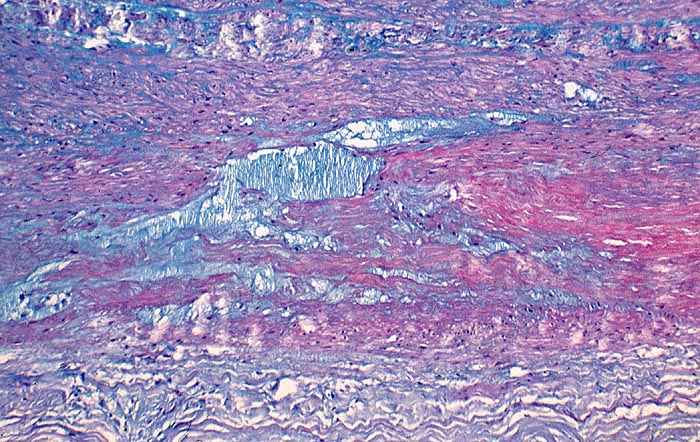

Zystische Mediadegeneration Erdheim Gsell

Pseudozystische Degeneration der Media. Die zystischen und spaltförmigen Hohlräume sind aufgefüllt mit alcianblauen Mukopolysacchariden.

Besonders häufig kommt die zystische Mediadegeneration beim Marfan Syndrom vor. Sie gilt als wichtiger prädisponierender Faktor für ein Aneurysma dissecans der Aorta.